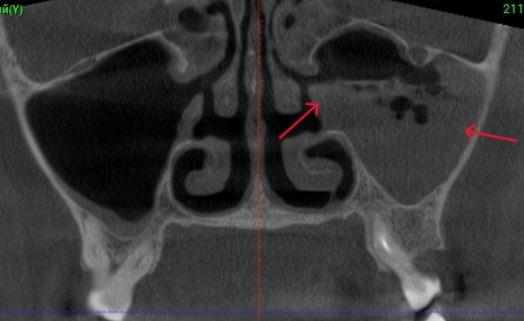

Важливо: Якщо нежить триває понад 2 тижні, з’явилася температура, набряк обличчя чи біль в очах — не відкладайте візит до ЛОРа. Раннє КТ пазух носа дозволяє виявити приховані кісти, поліпи, сторонні тіла або одонтогенний гайморит ще до ускладнень.

КПКТ (конусно-променева комп’ютерна томографія) — це 3D-знімок високої роздільної здатності. На відміну від звичайного рентгену, КТ показує:

КТ дозволяє провести віртуальну операцію: встановити імплант у програмі, виключивши будь-які ризики травмування пацієнта.